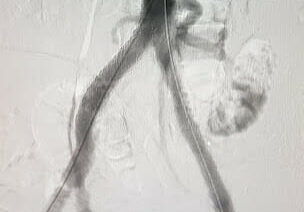

Gore Viabahn VBX Covered Stent plays important role in addressing complex aorta-iliac occlusive3

Gore Viabahn VBX Covered Stent plays important role in addressing complex aorta-iliac occlusive.

Is Gore VBX a better alternative for CERAB reconstructions2

Is Gore VBX a better alternative for CERAB reconstructions?

VBX as primary choice

VBX as primary choice for complex aorto-iliac reconstructions.